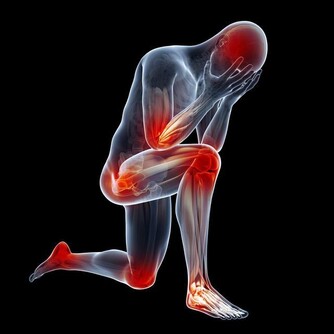

眾所周知,一旦大家走路走的久了膝蓋就會酸。但是,很多人都不了解為什麼走路久了膝蓋會酸。隨著社會的發展,現在越來越多的人鍛煉身體,而大多數人們選擇鍛煉身體的方式為跑步。因為跑步可以隨時隨地進行,也不需要藉助任何東西,所以大家都更多的喜歡選擇這種方式來釋放壓力和健身。

然而,跑步久了對人體真的有好處嗎?事實證明不然。大多數人剛開始跑步都有同樣的感受膝蓋酸。跑步久了相當於一項大運動,此時的肌肉細胞運動旺盛進行無氧呼吸產生乳酸,乳酸堆積過多就會讓人覺得酸痛。如果每天都堅持跑,過段時間膝蓋酸的情況就會消失,這是因為乳酸被分解了的緣故。

當然,走路久了也是個道理。跑步過度或者不當,可能會導致膝關節炎和勞損、扭傷或滑膜炎等炎症產生,給自身帶來麻煩。走路時間久了,也可能會導致膝關節病變,從而引發相關的炎症。因此,大家在長時間走路或者跑步的同時需要適度、適當的中途休息,不可忽視膝蓋發出的“信號”。

當人們長期性的走路久時,下肢靜脈壓力相應的較低,下肢靜脈,淋巴液回流受阻,從而引起膝蓋酸腫,因而走路久了需要休息。如果長期性走路久了引起膝蓋酸痛,就需要到正規的醫院對膝蓋部位做x光片檢查骨質情況,再聽醫生的話進行治療。

值得注意的是,膝蓋痛有可能是缺鈣、涼風寒濕痺證、骨質增生、受涼受風受濕、肝腎虛弱等所引起的。隨著年齡的增長,站立或者走路久了,膝關節都可能會發生退性行病變。初期,起病緩慢者膝關節疼痛不嚴重,可持續性隱痛,氣溫降低時疼痛加重,與氣候變化有關。

晨起後開始活動,長時間行走,劇烈運動或久坐起立開始走時膝關節疼痛僵硬,稍活動後好轉,上、下樓困難,下樓時膝關節發軟,易摔倒。蹲起時疼痛,僵硬,嚴重時,關節酸痛脹痛,跛行,關節功能受限,以下蹲最為明顯,伸屈活動有彈響聲,部分患者可見關節積液,局部有明顯腫脹、壓痛現象,合併風濕病者關節紅腫、畸形。

總之,為了健康,大家應該避免長期劇烈運動,適當的進行體育鍛煉,及時治療膝關節損傷。